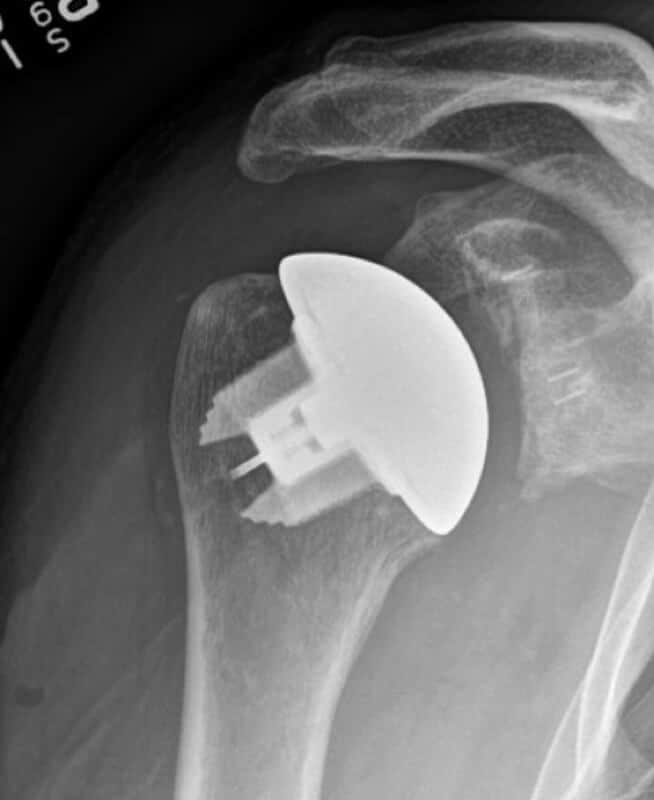

DJO/Enovis, CS Edge